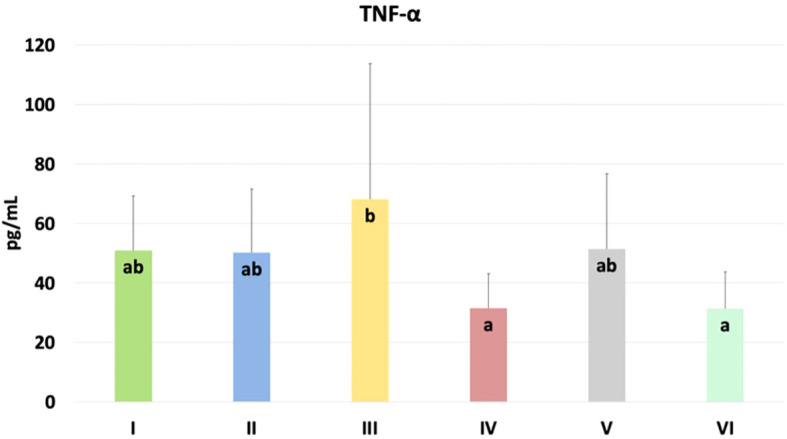

The results of selected indicators of epigenetic and oxidative changes in chicken blood plasma are shown in T2. Significant differences in tumor necrosis factor-alpha (TNF-α) levels are shown in f8. TNF-α levels were significantly higher in the group challenged with CBD, compared to the nano-Se + C. perfringens and CBD + nano-Se + C. perfringens groups (P=0.048). The difference between the group challenged with both additives and the C group was not significant. No significant differences were shown in the other assays.

| TNF-α [pg/mL] | 50.890ab | 50.160ab | 68.170b | 31.550a | 51.370ab | 31.450a | 13.946 | 3.898 | 0.048* |

In the current experiment, epigenetic, immunological and oxidative changes as a response to treatment in the blood and jejunum of chickens were investigated. TNF-α is an important pro-inflammatory cytokine that plays a key role in immune responses during infection. It helps initiate and regulate the immune system response by promoting inflammation, cell survival, and elimination of pathogens. However, dysregulation or overproduction of TNF-α may contribute to chronic inflammation (ref. 57, ref. 58). In blood, significantly higher TNF-α in the CBD + C. perfringens group was found compared to the nano-Se + C. perfringens and CBD + nano-Se + C. perfringens groups. This may show a specific effect of this compound on the immune system. The increase in TNF-α levels may be related to an increase in the inflammatory response induced by the infection and suggests that the CBD supplement, rather than having an immunosuppressive effect, may have increased the inflammatory response in the context of this infection. Still, it should be noted that no significant difference was found between the control group and the infected group with one or two supplements. CBD is well known for its immunomodulatory effects (ref. 59, ref. 60), but there are studies indicating that in the bacterial response, it may also induce an increase in the production of pro-inflammatory cytokines (ref. 61, ref. 62). The increased TNF-α levels in the CBD-infected chicken group may be the organism’s attempt to counteract the stress stimuli through an enhanced inflammatory response. In this study, TNF-α expression was not altered by the C. perfringens challenge (C vs. C. perfringens group), which agrees with previous studies (ref. 63–ref. 65). The difference in TNF-α levels between the group of chickens supplemented with CBD alone and the group supplemented with both nano-selenium and CBD may be due to the synergistic effects of the two compounds. Nano-selenium, through its antioxidant and immune response modulating effects, may have reduced the pro-inflammatory effects of CBD alone, explaining the lower TNF-α levels in the group with the combination of these supplements, which is consistent with the results of Sendani et al. (ref. 66). On the other hand, the lack of a significant difference between the control group and the infected group with the addition of both nano-selenium and CBD may suggest that the combination of these two compounds has a balanced effect on the immune system, mitigating the excessive inflammatory response caused by the infection, allowing for a more controlled immune response. On the other hand, in the gut, significant differences were shown in the expression of Casp 3, IgY, and % of methylated DNA. Caspase 3 is a key enzyme in the process of programmed cell death (apoptosis). Casp 3 activation is often triggered in response to various stressors, leading to controlled cell death that helps maintain homeostasis and eliminate damaged cells (ref. 67). In this study, Casp 3 levels were significantly lower in the control group compared to the C. perfringens, nano-Se + C. perfringens, and CBD + nano-Se groups. This result contrasts the study of Guo et al. (ref. 46), who found a lack of significance in Casp 3 levels in C. perfringens-infected chickens. In contrast, this result aligns with the study by Huang et al. (ref. 68), which showed that infections can significantly increase caspase 3. However, the increase in this factor in the CBD + nano-Se and nano-Se + C. perfringens groups is not easy to explain. The possible action was that nano-selenium at the dose used in the experiment exhibits a pro-apoptotic effect, perhaps to accelerate the elimination of damaged cells. It is important to note that no significant differences were shown between the control group and the CBD + C. perfringens and CBD + nano-Se + C. perfringens groups, which is consistent with a study by de Fillips et al. (ref. 69), which showed that CBD reduces inflammation in patients with LPS-induced colitis and lowers Casp 3 levels. It can also be concluded that the beneficial effect of nano-selenium, in this case, may depend on synergism with cannabidiol, or cannabidiol could have reduced the potential pro-apoptotic effect of nano-selenium. Evaluation of the immunoglobulin Y concentration showed that it was significantly lower in all test groups compared to the control and non-infected group with cannabidiol and nano-selenium. In poultry, IgY is a type of special immunoglobulin that is produced by stimulation of specific antigens in vivo and has a similar function to immunoglobulin G (IgG) in mammals (ref. 70). However, very limited information is available on this immunoglobulin and C. perfringens infection in poultry and its concentration dependence on nano-selenium and cannabidiol. Decreased IgY concentrations in chickens with bacterial infections may indicate an impaired immune response, favoring further infection and intestinal barrier damage. This is consistent with a study by Cui et al. (ref. 70), who showed reduced levels of IgY mRNA expression in the jejunum after LPS treatment of E. coli in chickens. Contemporary research confirms that IgY supplementation in the context of pathogen control may have a supportive effect. Still, it may sometimes be ineffective, which may explain the lower concentration of this immunoglobulin in the study groups (ref. 71, ref. 72). Interestingly, IgY concentration in the control group and the non-infected group with the addition of CBD + nano-Se was at the same level. This indicates that the addition of cannabidiol and nano-Se does not, by themselves, reduce the concentration of IgY in chickens. The % of methylated DNA was significantly higher in the infected group compared to all other study groups, which is consistent with the results of Ognik et al. (ref. 11), which showed that C. perfringens infection increased the percentage of methylated DNA in the wall of the ileum in turkeys. DNA methylation is a key process regulating gene expression, which affects many cellular functions, including immune response, cell growth, and stress response. Evidence from in vivo and in silico studies shows that cannabidiol can regulate the activity of enzymes responsible for DNA methylation due to its direct binding to the enzymes and/or regulating their activity through neurotransmitter-mediated signaling (ref. 19, ref. 73). In a rodent model of iron-induced neurodegeneration, CBD normalized mitochondrial DNA methylation levels in the hippocampus (ref. 73). Toubhans et al. (ref. 74) showed that selenium can modulate histone methylation, highlighting its important role in redox biology. Both assumptions are consistent with the current results, as the results in the infected groups with additives and the control group were at similar levels. Given the above, it may be concluded that the lack of significance in the assays of the other parameters indicative of epigenetic and oxidative changes may be related to two main facts: (i) the C. perfringens infection was not sufficient to induce the full changes in the parameters studied, and (ii) the exposure to challenge factor was too short to bring about the aforementioned changes fully.